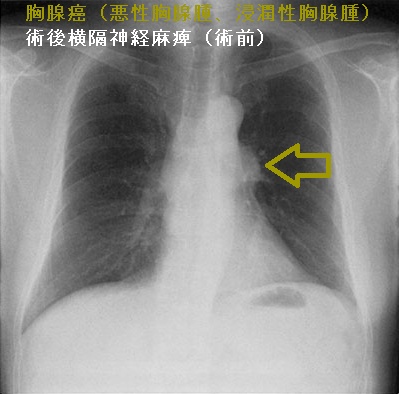

胸腺癌(悪性胸腺腫、浸潤性胸腺腫)

胸腺癌(悪性胸腺腫、浸潤性胸腺腫)は非常に稀で、標準的な治療が存在しません。組織型も、扁平上皮癌・未分化癌・小細胞癌と多様です。甲状腺機能亢進症/バセドウ病に合併した

胸腺癌(悪性胸腺腫、浸潤性胸腺腫)は前胸部から肺門部まで浸潤し、横隔神経自体にも浸潤するため、摘出手術で横隔神経を損傷する可能性が高い(術後横隔神経麻痺)。術後横隔神経麻痺では、術後から息が深く吸えなくなります。内肋間筋・補助呼吸筋と代償性の呼吸数増加で補える場合が多いが、重症例は胸腔鏡下横隔膜縫縮術の適応。